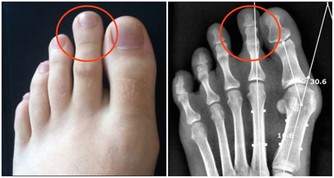

臨床研究發現,人體隨著年齡的增長骨骼中的鈣會隨著流失,從而導致骨質疏鬆等病症,骨質疏鬆為例,50歲以上的發病率為28%,60歲以上的發病率為58%,80歲以上的發病率會高達100%,除了年齡增長必然的鈣質流失外,生活中還有一些飲食上的因素會偷偷的帶走身體中的鈣。所以臨床中有很多案例,吃了將近一年的多的鈣片後去體檢反而骨密度降低了,其實這種情況很有可能是出在了飲食上。那麼究竟是哪些食物能帶走鈣呢?